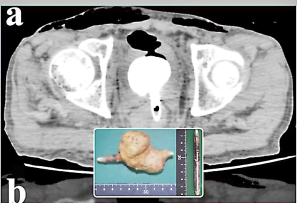

या व्यक्तीचे नाव काही कारणामुळे गुप्त ठेवण्यात आले आहे. तो एक 60 वर्षांचा प्रौढ गृहस्थ होता. त्याला असह्या पोटदुखीमुळे त्यांच्या कुटुंबियांनी रुग्णालयात आणले होते,. दोन दिवस प्रयत्न करुनही त्याच्या पोटदुखीचे निदान होऊ शकले नाही. त्यामुळे उपचारांना प्रतिसाद न मिळाल्याने त्याचा मृत्यू झाला. त्याची उत्तरीय शल्यचिकित्सा (पोस्ट मार्टेम) करण्यात आले. त्याच्या आतड्यात एक ‘आयलायनर’ नावाचे साधन सापडले. अनेक दिवसांपासून ते तेथे अडकले असावे. कारण त्या साधनाला लागून एक गाठही विकसीत झाली होती. यामुळे त्याच्या मूत्रपिंडांवर दाब येऊन त्यांनी काम करणे बंद केले होते. परिणामी, त्याचा मृत्यू झाला. त्याच्या पोटात अडकलेला आयलायनर अॅल्य्मिनियमचा असून तो जवळपास 8 मिलीमीटर रुंद होता. तो काढण्यात आला. मात्र, तो त्याच्या पोटात शिरला कसा, याचे डॉक्टरांनाही आश्चर्य वाटत होते. या प्रकाराचे अन्वेषण करण्यात आले, तेव्हा या व्यक्तीच्या काही विचित्र आणि विकृत सवयींचा उलगडा झाला. त्याला महिलांची वस्त्रे आणि आतली वस्त्रे परिधान करण्याचा नाद होता. तसेच, त्याला काही लैंगिक साधनांचाही (व्हायब्रेटर्स) उपयोग करण्याची सवय जडली होती. अशाच विकृत प्रयत्नांमध्ये तो आयलायनर त्याच्या आतड्यांमध्ये शिरला आणि तो त्याला काढता न आल्याने त्याला प्राण गमवावा लागला आहे.